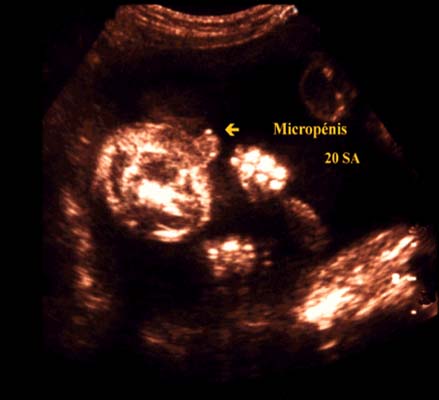

Son diagnostic est subjectif car il n’existe pas de table de croissance. La principale difficulté étant de ne pas le confondre avec un gros clitoris.

La distinction entre un scrotum et des bourrelets labiaux aidera au diagnostic.